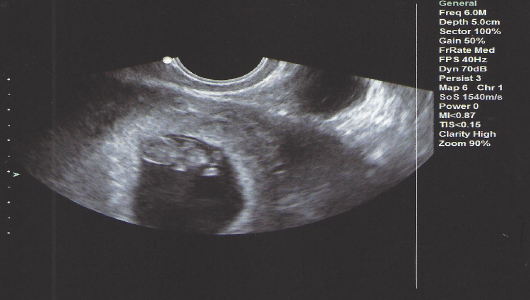

I got to see my two little ones and hear their heartbeats again this week at 7w4d. They are pretty clearly di/di. I "graduated" from the REs office and cried in the elevator leaving, it was really overwhelming. Sorry to keep posting all my ultrasound photos but staring at them is the only thing that keeps me from losing my mind with all the nausea and vomiting. And we haven't told anyone else so I have to keep telling you all!